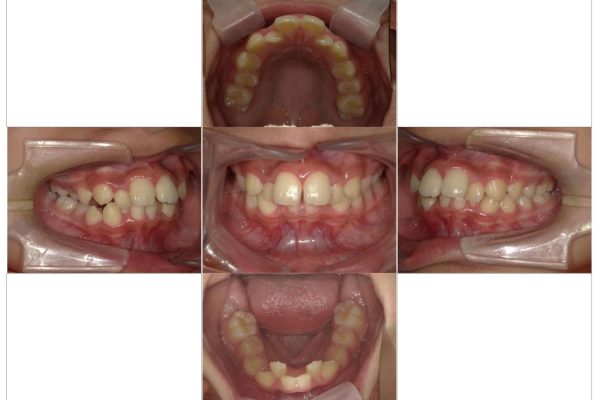

2026.1.26 / 施術例

インビザライン症例

あけましておめでとうございます。 本年もまるやま歯科医院をよろしくお願いいたします。   久しぶりの矯正の症例になります。 患者さ・・・